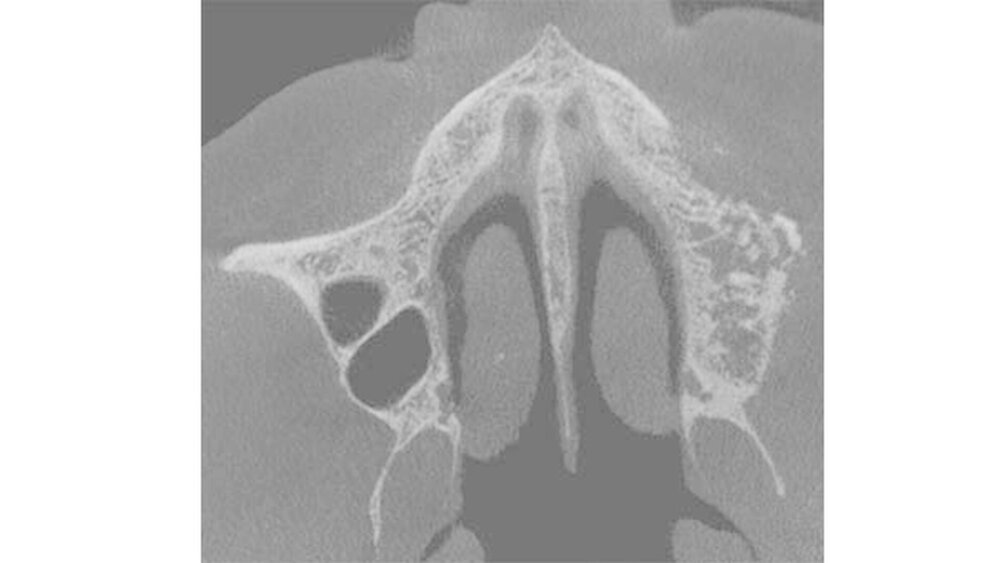

Im Frühjahr 2016 trat dann jedoch unter einer Brücke eine Knochennekrose im Oberkiefer links auf, die bei der Patientin Schmerzen und einen unangenehmen Geschmack im Mund verursachte. In Absprache mit der behandelnden Onkologin wurde der OP-Zeitpunkt festgelegt und nach einer Zytostatika-Pause erfolgte der MKG-chirurgische Eingriff in Narkose und unter kontinuierlicher Antibiotika-Therapie mit plastischer Deckung des Knochens.

Die Wundheilung verlief zunächst verzögert und etwas schleppend, aber letztendlich erfolgreich. Die Patientin behielt ihren Kiefer und wurde beschwerdefrei.